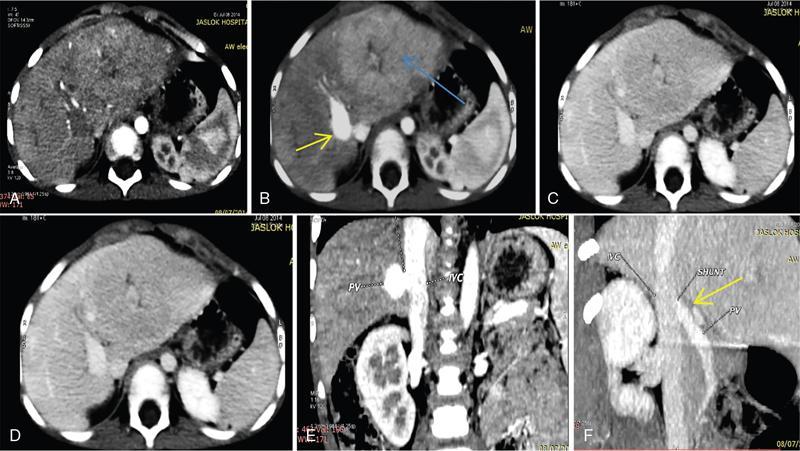

Ritu K. Kashikar, Shrinivas B. Desai, Payal Agrawal A spectrum of vascular variants can involve the liver. Both congenital and acquired anomalies can be seen. The abnormalities can involve the portal venous system, hepatic artery, hepatic veins or maybe the result of shunting between any of these vessels. Though not commonly encountered, familiarity with the pathogenesis and imaging features of these vascular entities can guide appropriate patient management. This chapter aims at classification of vascular pathologies of the liver (Table 9.12.1) with description of important entities. The umbilical vein accounts for approximately 80% of the afferent flow into the liver in utero. The umbilical vein joins the left portal vein, which in turn drains into the ductus venosus and carries blood to the inferior vena cava. The umbilical vein and ductus venosus start involuting at birth and typically close in the first week of life in term neonates (Fig. 9.12.1). Detailed embryology of the portal venous system has been discussed in previous chapters. The portal vein accounts for two-thirds of the hepatic blood supply. The distinctive feature of the portal vein is that it begins and ends in capillaries. The blood from the entire gastrointenstinal tract (except lower rectum), gallbladder, pancreas and spleen is carried via the portal vein to the liver. The hepatic arterial branches divide along the distribution of portal venous radicals and supply oxygenated blood to the sinusoids (Fig. 9.12.2). These include The dorsal and ventral limbs of the vitelline vein form the normal portal vein. Atrophy of the ventral limb occurs during embryogenesis. This maybe an incidental finding, though association with duodenal obstruction is seen in 50% cases. The aetiology of duodenal obstruction is often due to secondary causes such as duodenal stenosis, atresia, Ladd bands due to malrotation or annular pancreas. Associations include heterotaxy (polysplenia) and biliary atresia. Aberrant vessel may give an extrinsic impression on the high second portion of the duodenum on upper GI series. USG may show aberrant vessel in patients being scanned for other anomalies. The aberrant vessel is usually incidentally discovered intraoperatively during surgery for duodenal obstruction or malrotation. Hypoplasia or atresia of the portal vein may involve all or a portion of the portal vein. Atresia of a major branch is associated with absence of the corresponding hepatic lobe. Main portal vein hypoplasia or stenosis results in prehepatic portal hypertension and gastrointestinal hypertension (Flowchart 9.12.1). A portal vein smaller in calibre or as small as the adjacent hepatic artery is termed hypoplastic. The venous diameter in cases of hypoplasia is of 3 mm. Twenty-six per cent cases with biliary atresia have hypoplastic portal vein. TAPVR is a congenital cardiac malformation in which pulmonary veins instead of draining into left atrium during cardiac development, drain into the right atrium via an anomalous vein, resulting in right to left shunts. Types: In type 3 TAPVR an anomalous infradiaphragmatic vertical vein is formed by the confluence of pulmonary veins, typically through the oesophageal hiatus. Venous obstruction at the level of the diaphragm and accounts for the clinical presentation of pulmonary venous congestion and oedema. Early presentation (within 24–36 hours of life) included respiratory distress with cyanosis, tachypnea, and tachycardia. Features on X-ray include normal–sized heart with pulmonary interstitial oedema. One-third of patients have an additional complex cardiac anomaly and heterotaxy with right atrial isomerism. May show abnormal draining vein draining into the IVC or pulmonary vein. CT/MR venography allows accurate depiction of the anomaly. The pulmonary venous confluence drains to systemic veins below the diaphragm. The confluence is usually posterior to the left atrium and vertically oriented. From here, a descending vein passes through the oesophageal hiatus and most frequently drains into the connection in to ductus venosus, hepatic veins or inferior vena cava is not as frequent. Portosystemic shunts are classified into intrahepatic and extrahepatic. In the intrahepatic shunts, the shunt is at the level of PV branches after its division whereas in the extrahepatic shunts the anastomoses are between the tributaries of the portal or mesenteric system or main PV and a systemic vein (Flowchart 9.12.2). Abernethy malformation, also known as congenital extrahepatic portosystemic shunts (CEPS) is a rare clinical entity, in which portal blood is shunted partially or completely into the systemic circulation via an abnormal communication of the portal system with the systemic circulation. It results from persistence of embryonic vessels. The entity was named by John Abernethy in 1793. The embryological development of the portal vein occurs between the 4th and 10th weeks. The umbilical veins of chorionic origin, vitelline veins and the cardinal veins from the body of the embryo are the three paired venous systems seen in the embryo in the 4th week. Communications develop between the vitelline veins at 4 weeks, which anastomose to form a figure-of-eight configuration around the developing duodenum. Selective involution of these veins leads to the final configuration of the portal vein. Because the vena cava also has a complex development and is derived from several venous channels including the sinus venosus and a portion of the anastomosis between the right and left vitelline veins in the cranial part of the liver, it has been suggested that this may be the embryological basis of development of congenital extrahepatic portosystemic shunts. Various systems have been proposed for classification of Abernathy Syndrome: In this classification portal flow is classified as Patients with type A drainage show associated cardiac anomalies, while gastrointestinal bleeding is common in type C. In this system CEPS was classified into three types depending on the degree of severity of intrahepatic portal system hypoplasia in to mild, moderate and severe types. This system has therapeutic implications in providing information regarding acceptance of portal blood flow by the portal vasculature after shunt occlusion. CEPS may be asymptomatic well into adulthood and many authors have reported seeing adult patients presenting for the first time with clinical manifestations. Clinical features of portosystemic shunts may broadly be divided into: These include hepatopulmonary syndrome, metabolic dysfunction and hepatic encephalopathy. Patients with type 1 shunt have a female preponderance and often have concomitant congenital anomalies. These anomalies are less common in patients in type 2 shunts. Other anomalies have also been reported in patients with Abernethy malformation which include chromosomal anomalies such as Downs syndrome and structural anomalies of the heart, gastrointestinal, genitourinary, skeletal and vascular systems. Approximately half the patients of CEPS have nodular lesions of some sort in the liver (Flowchart 9.12.3). Nodular hepatic lesions in patients with congenital portosystemic shunts may be single or multiple. In order to establish a diagnosis of CEPS a communication between the portal and the systemic venous system, either before or after the formation of the PV by union of the SMV and SV has to demonstrated. Secondary causes of nonvisualization of the PV such as portal cavernoma or PV thrombus should be excluded. Patients with congenital portosystemic shunts do not have features of portal hypertension, such as splenomegaly, varices and collaterals. USG may demonstrate the shunt and show haemodynamics involved such as the magnitude and direction of flow. It may pick up congenital shunts preoperatively; however, it may not detect associated anomalies particularly of lung and heart. Smaller shunts, particularly type 1a may not be well picked up. Ultrasound may not fully characterize liver lesions seen in these patients. It is the modality of choice and can accurately diagnose the shunt and type and aids in management. Shunt is visualized as an abnormal communication between the portal venous and systemic circulation and is best depicted in the portal venous phase. CT also shows presence/absence of intrahepatic branches of portal vein. Evaluation of associated anomalies particularly in patients with congenital heart disease who require evaluation of pulmonary vasculature, or patients with suspected hepatopulmonary syndrome who require evaluation of the lungs can also be done with CT (Fig. 9.12.4 and Table 9.12.3). Another major advantage of CT is that it helps to detect and characterize hepatic lesions in these patients. It displays the arterial and venous anatomy, and provides an angiographic road map for surgical resection. Regenerative nodules are usually homogeneous with enhancement during arterial phase, on both CT, however without washout (Fig. 9.12.5). Rest of lesions show classic enhancement pattern as described in previous chapters. The imaging findings in patients with Abernethy malformation with hepatocellular carcinoma do not appear to be typical, that is hypervascularity on the arterial phase images with washout on delayed phase. Thus, patients who do not have typical findings of a benign lesion, that is lack of arterial enhancement, should be closely followed up or biopsied. Disadvantages of an MRI include longer periods of sedation which is a disadvantage in patients with CEPS who may be very young, very hypoxemic or encephalopathic. MRI also has lower spatial resolution than CT and may not show small intrahepatic portal venous radicles in type 2 patients. MRI can otherwise show all abnormalities seen on CT. Advantages of MRI using hepatobiliary contrast agents are in the characterization of hepatic nodules and for follow-up. MRI does not expose the patients to ionizing radiation. Patients with no symptoms, those with mild metabolic abnormalities and with liver nodules should be followed up with ultrasound and biochemistry. Patients with portosystemic encephalopathy, liver dysfunction or those with shunt ratio >60% should be treated according to type of shunt. Patients with type 1 shunts should be transplanted. Patients with type 2 shunts should be treated with shunt closure – either via embolization or surgical. Liver transplantation is considered when medical and surgical methods fail especially in patients with complications. Intrahepatic portosystemic shunts are rare. They may be congenital or result from trauma or portal hypertension. They develop due to persistent communications between vitelline and umbilical systems. These are communications between the branches of the PV and inferior vena cava (IVC). Park et al. classified these 1990 in four types. Type 5 was added later, these are classified in Table 9.12.4. Type 2 shunt with or without a focal varix is the most common type reported. Another classification system is proposed by Kanasawa et al. based on correlation with severity of portal hypoplasia (mild, moderate and severe) with portal venous pressure, histopathological findings, postoperative portal venous flow and hepatic regeneration. Associated anomalies such as cardiovascular, hepatobiliary, urogenital and gastrointenstinal can be seen. Complications such as portopulmonary hypertension are seen in 13%–66% children. As a consequence of long-term shunting, hepatic encephalopathy, and hepatopulmonary syndrome are the most common symptoms. Tumours such as FNH and regenerating nodular hyperplasia can be seen. These shunts may close spontaneously within the first 2 years of life or may remain asymptomatic and undetected for several years. When chronic shunting persists into adulthood, patients most often present with encephalopathy. The feeding (afferent) and draining (efferent) vessels of the shunt appear as enlarged, tubular, anechoic structures that are contiguous with the portal and hepatic veins. Antegrade flow is seen on colour Doppler images. Focal varix if present appears as an abnormal, rounded cystic structure with turbulent flow. Doppler study can also calculate the shunt ratio (total blood flow volume in the shunt divided by the blood flow in the portal vein). Shunt ratios greater than 60% should be corrected to prevent complications. Loss of normal undulating waveform of afferent portal vein branch with increased flow velocity and phasic waveforms owing to transmitted cardiac pulsations can be seen. The efferent hepatic vein branch of the shunt can show continuous flow with flattening of the Doppler waveform due to increased portal venous inflow. Communication between intrahepatic portal venous and peripheral hepatic venous radicals can be demonstrated easily on both contrast-enhanced CT and MRI. Similar to extrahepatic shunts CT is preferred over MRI in documentation of shunts. The afferent portal vein branch and the efferent hepatic vein branch are enlarged. Venous varices can be seen. The draining hepatic vein branch opacifies earlier than other hepatic veins (Fig. 9.12.6 and Table 9.12.5). The liver may show fatty degeneration and atrophy, but when the anomaly is corrected, fatty replacement disappears and liver size increases. Conservative medical therapy including restriction of protein and ingestion of lactulose. Symptomatic intrahepatic portosystemic shunts can be managed conservatively or with transcatheter embolization, surgical ligation or partial hepatectomy. The connection between the left umbilical vein and right hepatocardiac vein (future IVC) in the foetal circulation is called ductus venosus. This vessel is responsible for carrying nutrient-rich blood from placenta to the right atrium directly by bypassing the sinusoidal plexus of the liver. The umbilical vein and ductus venosus close at birth and form the ligamentum teres and ligamentum venous, respectively. The time interval following birth for closure of ductus venosus is variable ranging from few minutes after birth to 18 days in term neonates and as late as 37 days in premature infants. Patent ductus venosus is an intrahepatic portocaval shunt causing partial or complete diversion of portal blood to the systemic circulation and may present with hyperammonemia. Patent ductus venosus is seen on Doppler sonography as a vascular tubular structure in the left lobe of the liver, continuing from the umbilical vein and connecting the portal vein to the inferior vena cava. The foetal ductus venosus show waveforms similar to IVC corresponding to the cardiac cycle with a systolic and diastolic component. This diphasic waveform is seen in preterm and term infants and becomes monophasic as ductus closes. CT and MRI also accurately detect the shunt and patency. Associated hepatic lesions seen in patients with portosystemic shunts can be diagnosed and characterized better. Treatment (closure) is recommended in cases with complications or to prevent complications if the shunts persisted beyond 2 years of age. Shunt closure can be performed surgically or endoscopically. The complex nature of the shunt can pose problems during surgical closure. Transvenous and balloon occlusion have been done successfully. Occlusion of portal vein can occur due to a variety of conditions. The aetiologies of portal venous thrombosis in the neonatal age group include umbilical vein catheterization, omphalitis, dehydration or neonatal sepsis. Older children develop occlusion secondary to intraabdominal infections and portal hypertension. Other aetiological factors include prothrombotic states such as hereditary deficiency of protein C or protein S and factor V Leiden deficiency, vascular injury, trauma, stasis and congenital anomalies such as webs. Acute portal vein thrombosis can be asymptomatic, or the patient may present with abdominal pain, ascites or fever. Chronic portal vein thrombosis presents as ascites, encephalopathy, varices and upper gastrointestinal bleeding. Acute thrombus appears hypoechoic filling defect on USG with absent flow on Doppler. There is distension of the thrombosed vein (Fig. 9.12.7). CT and MRI with contrast will detect filling defect in the vein with distension. T2W1 images may show absence of flow void. Acute thrombus may appear hyperintense on T1W1 images. Tumour thrombus reveals signal similar to tumour on all sequences with diffusion restriction (Fig. 9.12.8). Chronic thrombus may present as eccentric filling defect, attenuation of vein or less commonly calcification of vessel wall. Collaterals are often seen in chronic portal vein thrombosis. Treatment usually involves combination of anticoagulation and intervention depending on age of thrombus. An acute portal venous thrombus may undergo partial or complete spontaneous resolution. The commonest cause of paediatric portal hypertension in the developing world is extrahepatic portal vein obstruction (EHPVO). It is also the second most common cause of portal hypertension in the western world. EHPVO is a condition characterized by obstruction of the extrahepatic portal vein (as the name suggests) with or without associated involvement of the intrahepatic branches, splenic vein (SV) or superior mesenteric vein (SMV). The hallmark of this chronic longstanding condition is carvernomatous transformation of the portal vein. Acute and chronic portal vein thromboses occurring in the setting of liver cirrhosis or HCC are not included in this disorder. EHPVO is an important cause of noncirrhotic portal hypertension with preserved liver structure and function till late in course of the disease. Proposed aetiologies include infection or prothrombotic event occurring early in life (in genetically predisposed individuals), leading to portal venous occlusion (Table 9.12.6).